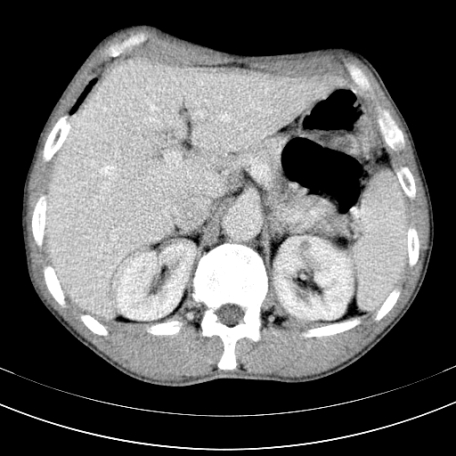

标题: CT21441:男55岁,上腹部胀痛半年余,请老师们看看是后腹膜淋巴 [打印本页]

标题: CT21441:男55岁,上腹部胀痛半年余,请老师们看看是后腹膜淋巴

眼拙!仅见胰腺稍丰满,脾大。

腹主动脉右侧有一个,有肿瘤病史吗?

腹膜后淋巴结肿大,原因待查。